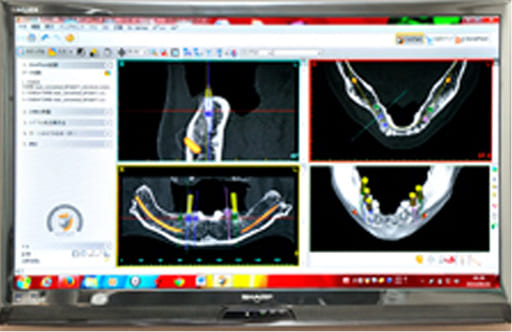

治療計画をさらに細かくし、インプラント周辺を重点的に検討・設計するのがインプラントプランニングです。

インプラントは一度埋入すると動かすことができません。

そのため、プランニングが適切でないと、周囲の歯が悪くなった結果、インプラントだけが取り残されてしまうケースもあります。この場合、上部構造を外してインプラントを使用しない状態にせざるを得なくなります。

そのような事態を防ぐためにも、事前の入念なプランニングが欠かせません。

インプラントを埋め込む際のドリル操作により、顎の骨を突き抜けてしまったり、神経を傷つけてしまったりするトラブルが起こる可能性があります。